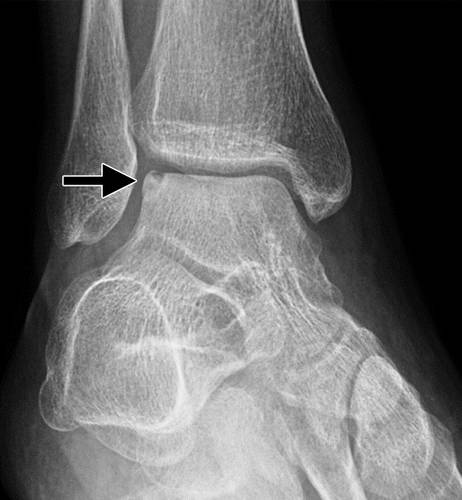

侧面病变往往是菲薄的和片形状,发生在背侧和反转损伤后(图11)。 内侧病变通常较少症状,通常是深和杯形,并且认为是源自跖屈和反转(图12)。 在稳定和无位移OCD片段中,毛细血管出芽可以发生在骨折线上并有助于愈合缺损,而移位的不稳定片段经常发生无血管坏死(25,29)。

图11b外侧距骨软骨骨折。 (a)踝关节的AP射线照片显示外侧的距骨穹顶(箭头)的微妙的骨软骨骨折,被重叠的腓骨遮蔽。 (b)脚踝的斜位视图更好地显示骨折(箭头)。

图12a内侧踝关节骨软骨骨折。 AP(a)和斜位(b)踝骨的X线照片显示椎间融合器的移位骨软骨骨折(黑色箭头)。 还注意到倾斜的骨干腓骨骨折(箭头),syndesmotic加宽(双头箭头)和内侧清晰空间加宽(白色箭头b),符合syndesmotic和三角肌韧带复杂损伤的存在。